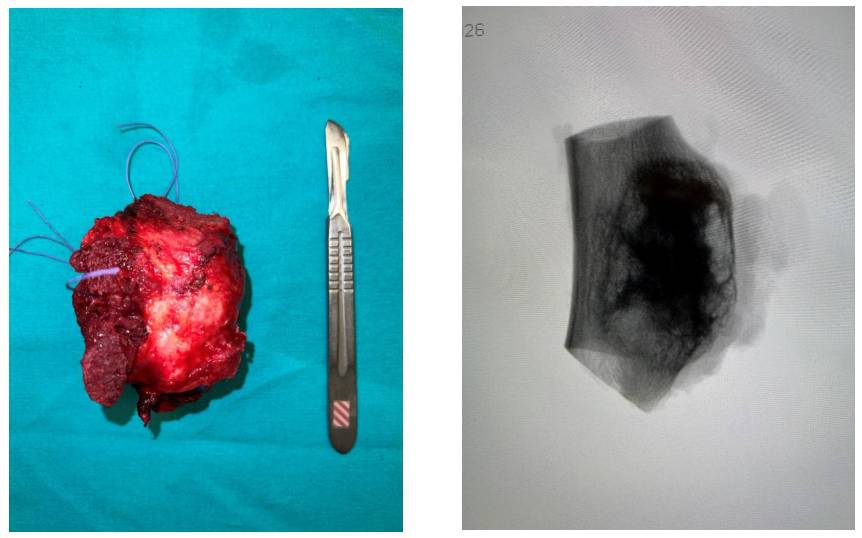

Ameliyat Esnası: Çıkarılan tümör dokusunun klinik ve radyolojik görüntüsü